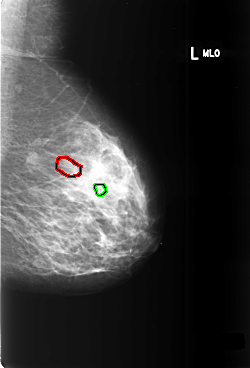

B_3400_1.LEFT_MLO

LEFT_MLO LINES 5880 PIXELS_PER_LINE 4000 BITS_PER_PIXEL 12 RESOLUTION 50 OVERLAY

FILE: B_3400_1.LEFT_MLO.OVERLAY

TOTAL_ABNORMALITIES 2

ABNORMALITY 1

LESION_TYPE CALCIFICATION TYPE PUNCTATE DISTRIBUTION SEGMENTAL

ASSESSMENT 4

SUBTLETY 3

PATHOLOGY BENIGN

TOTAL_OUTLINES 1

BOUNDARY

ABNORMALITY 2